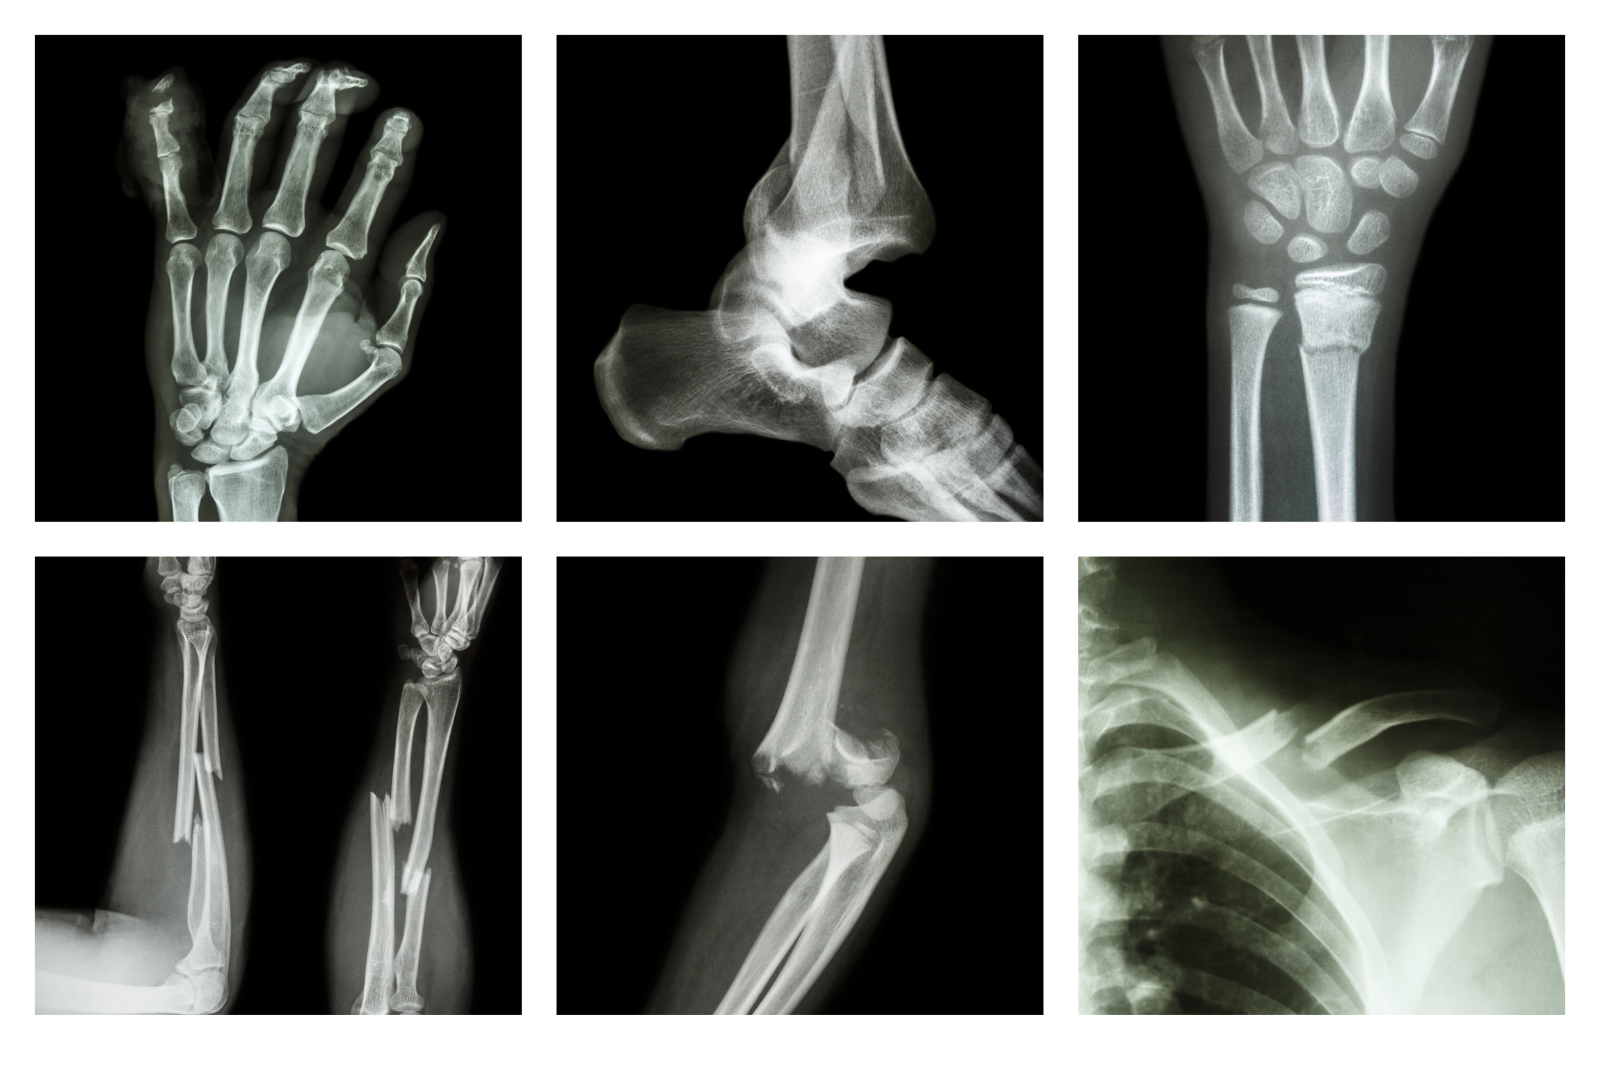

Фиксација на коска: Што значи, кога е потребна и како се одвива закрепнувањето

Фиксација на коска е медицинска постапка која се користи за стабилно спојување на скршена или оштетена коска, со цел да заздрави правилно. Таа може да биде внатрешна или надворешна и се применува при различни видови на фрактури или оперативни зафати.

Најчести типови на скршеници и очекувано време за закрепнување

1. Скршеница на колк (hip fracture)

●     Се јавува главно кај постари лица (особено жени со остеопороза)

●     Често бара хируршка фиксација со завртки или замена на зглобот (ендопротеза)

●     Период на закрепнувње е3–6 месеци и се препорачува ведаш започнување со физиотерапија и одење со помошни средства (шеталка/штаките)

2. Скршеница на зглоб на рака (distal radius fracture)

●     Се јавува кај лица кои паднале на испружена рака

●     Најчест третман е со гипс или плоча и завртки

●     Период на закрепнување е 6–8 недели и целосно враќање на подвижноста со помош на вежби

3. Скршеница на зглоб на глуждот

●     Се јавува кај млади и активни лица, спортисти

●     Третманот зависи од стабилноста; понекогаш е потребна внатрешна фиксација

●     Период на закрепнувње е 8–12 недели

4. Скршеница на бедро (femur fracture)

●     Третман е со помош на внатрешна фиксација со шипка или плоча

●     Време за закрепнување е4–6 месеци со рехабилитација интензивна и постепена